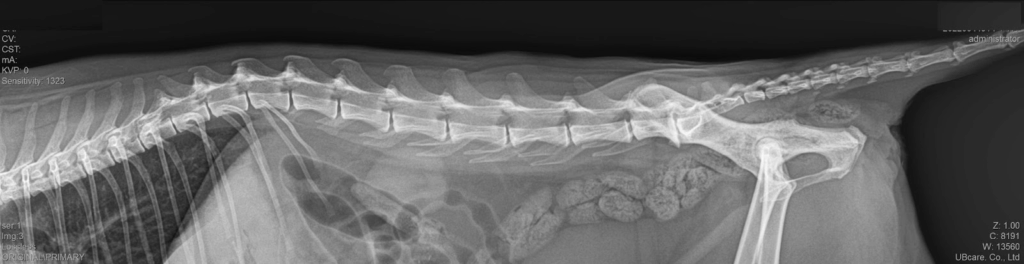

고양이 말총증후군(마미증후군) 치료 케이스 – 강서구 동물병원

고양이가 갑자기 점프를 하지 못하거나 뒷다리를 절뚝거리는 모습을 보신 적 있나요? 보호자님들께서는 단순 근육통이나 순간적인 삐끗으로 생각하기 쉽지만, 사실 신경계 질환일 수 있습니다. 그중 대표적인 질환 중 하나가 바로 말총증후군(Cauda Equina Syndrome, 마미증후군)입니다. 오늘은 본원에서 진단 및 치료를 진행한 실제 케이스를 공유드리겠습니다. 고양이 말총증후군 치료 케이스 이번 환자는 11살 중성화한 암컷 고양이로 체중은 5.3kg이었습니다. 내원 […]